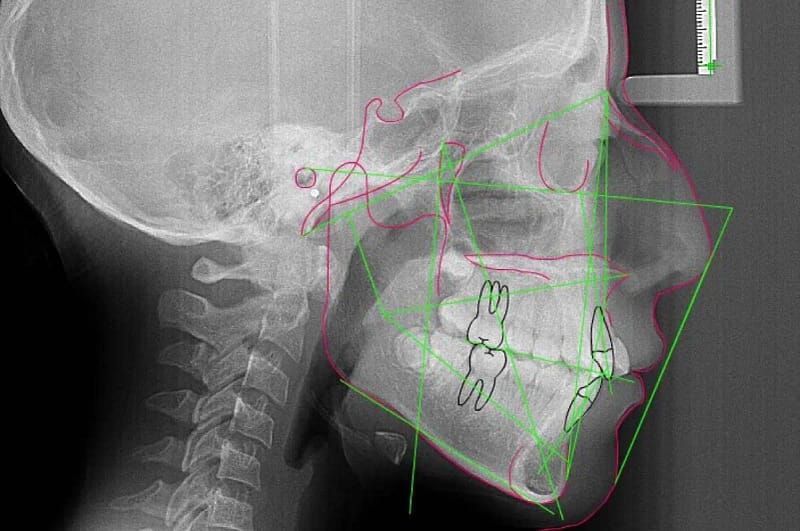

Somos una empresa con más de 5 años ofreciendo servicios de radiología oral y maxilofacial, fotografía intra y extra oral, toma de modelos (estudio y trabajo), análisis cefalométrico por parte de Radiólogos.